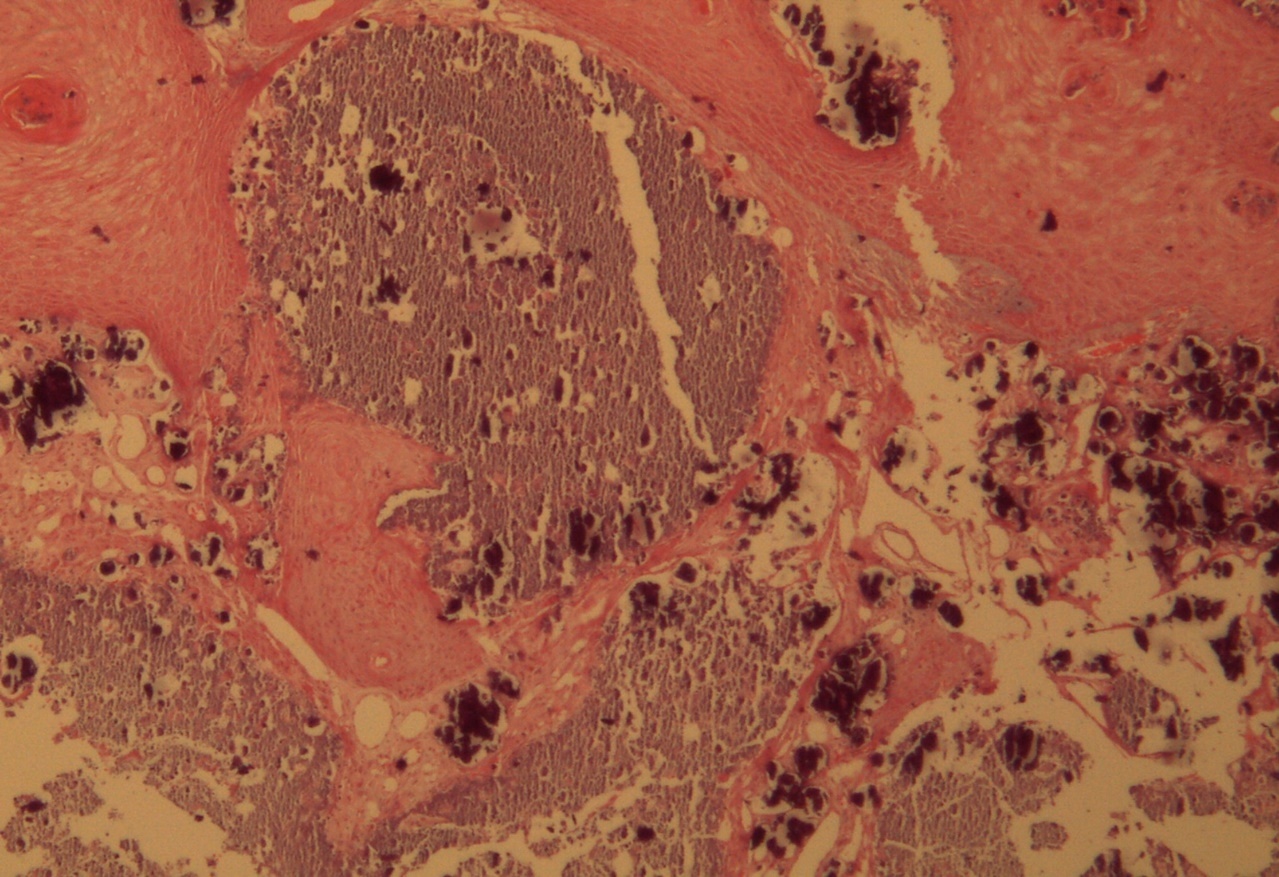

A 9-year-old male patient who was treated in the dermatology service for a progressively growing keratotic nummular dermal lesion on the right knee. With the clinical judgment of viral wart, the lesion was removed. In the Pathology Service, a nummular keratotic lesion of 0.5 cm in maximum dimensions was received, which crackled when cut. Figure 1, Figure 2, Figure 3, Figure 4, Figure 5

Figure 1.Hyperkeratosis, hypergranulosis, proliferation of dermal vessels, and surface and deep calcium deposits. HE. 100x.